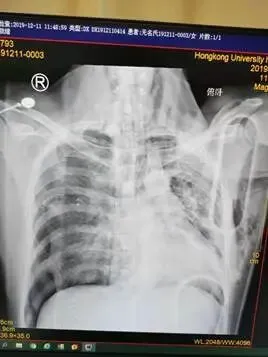

床边胸片:双肺挫伤,右侧气胸,双肺多发渗出;右侧3-5后肋、左侧2-7后肋多发骨折,左侧锁骨骨折。

影像科技师准备好拍片,完成床旁胸片、骨盆正位片,创伤团队即刻阅片,发现肺挫伤、右侧气胸,骨盆未见骨折。迅速于右侧第五肋间腋中线前放置胸腔闭式引流,有较多气体及少量血液引出。复测SPO2:75%,血压及心率无明显变化,末梢血循环正常,无紫绀。复查床旁胸片提示右肺没有完全复张、仍有气胸,压缩约30%,检查右侧胸腔闭式引流通畅、大量气体溢出,超声排除腹腔大出血、心包填塞可能,气管插管确定在气管内,呼吸机工作状态良好,无张力性及开放性气胸,使用储氧球囊接气管插管人工通气,发现气道阻力非常低,结合右侧胸腔闭式引流管有大量气体溢出,考虑右侧支气管损伤可能,患者SPO2继续下降至50%。立即予床旁纤维支气管镜检查,发现右侧主支气管挫伤及裂口,遂在支气管镜引导下行左侧主支气管插管并单侧肺通气,患者SPO2迅速升至98—100%,P112次/分,BP120/69mmHg。

CT提示右侧主支气管断裂,肺挫伤,多发肋骨骨折,左锁骨骨折,血气胸。遂急诊送手术室行胸腔探查、支气管断裂修补、左锁骨切开复位内固定手术。术后转重症监护室监护治疗,第三天评估患者病情稳定,脱机拔管,患者神志恢复,GCS15分,2周后痊愈出院,患者没有缺氧性脑病并发症。